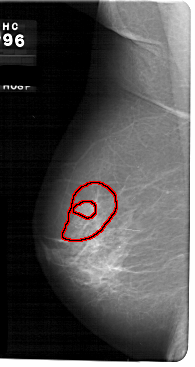

FILE: A_1726_1.LEFT_MLO.OVERLAY

TOTAL_ABNORMALITIES 1

ABNORMALITY 1

LESION_TYPE MASS SHAPE IRREGULAR MARGINS SPICULATED

ASSESSMENT 4

SUBTLETY 3

PATHOLOGY MALIGNANT

TOTAL_OUTLINES 2

BOUNDARY

CORE